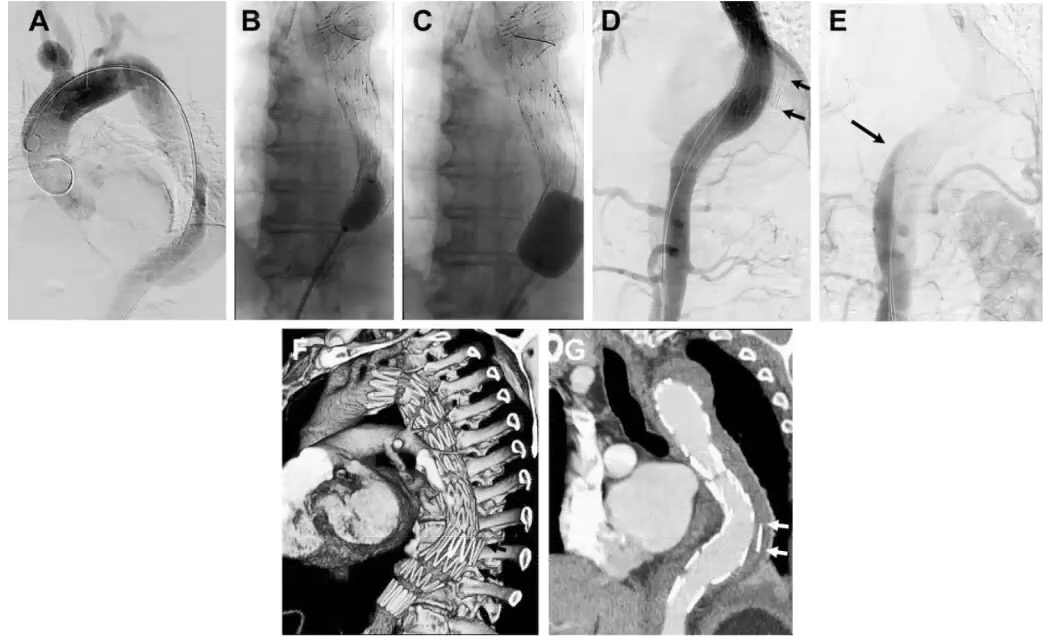

下图是论文中显示出球囊扩张的位置,即Knickerbocker段的示例图。

举一个在髂总动脉继发破口处进入假腔的一个例子:

使用IVUS定位导管进入假腔的位置,进行弹簧圈或者血管塞的栓塞,可以将其比作往“假腔里扔垃圾”。

术后CTA也显示“假腔内垃圾”的效果良好,成功堵塞了假腔。同时我们需要注意的是,在这个阶段正确的影像学辅助的重要性。

(术后CTA图)